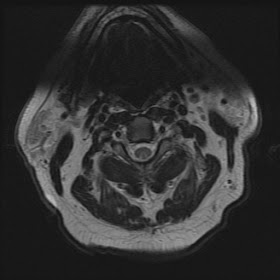

Axial T2 images of cervical cord shows increased T2 signal in both dorsal columns in the form of "inverted rabbit ears". Sagittal T2 images confirm increased T2 signal in the dorsal aspect of the cord corresponding to the location of the dorsal columns. Sagittal T1 with contrast shows no abnormal enhancement of the dorsal columns.

Radiological diagnosis of cervical myelopathy is based on the characteristic symmetrical T2 hyperintensity involving the dorsal columns seen as an " inverted V" or "inverted rabbit ears" on the axial plane. Variable contrast enhancement has been described. Although the findings are typical, SCD is a clinical diagnosis.